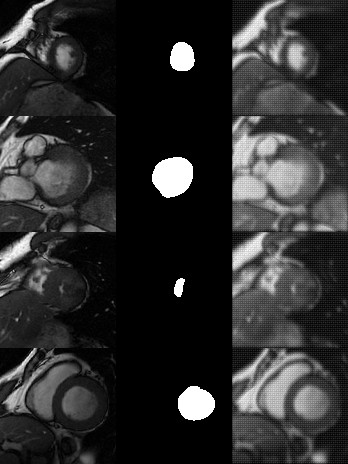

My data is a one channel double array, and my ground truth is the same, but with only 0s and 1s. Drawing the images is totally fine, but the network doesn't seem to care about the ground truth and just learns where in the input data/image the value is 0 (min value). The loss reduces over time, but then levels out at some epoch and the output doesn't change much. Typically after the first epoch, the network has learned where the "0"s are in the input data.

Any idea what could be wrong there? (below init, epoch 0, and epoch 10)

Init:

Epoch 0:

Epoch 10: